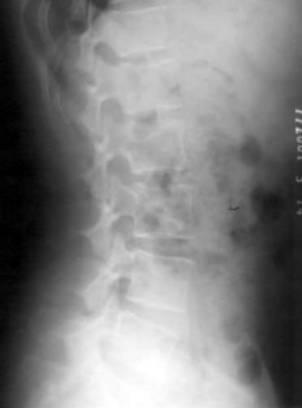

1、X线检查:脊柱曲度的改变;椎间隙变窄;椎体缘骨赘;关节突关节退变肥大;椎体滑脱;神经根管狭窄伴有椎间关节半脱位。

上椎体下缘的后延线不是穿越下椎体上关节突的端,而是穿过中间;正位片显示:正常的“S”弧线消失